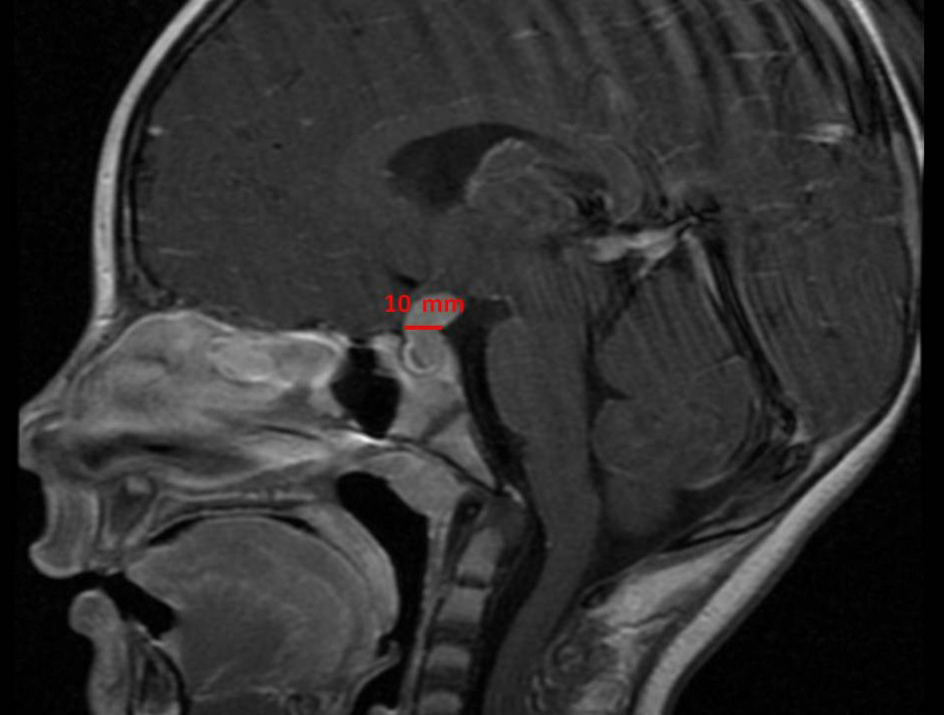

Una vez hecho el diagnóstico de diabetes insípida central, se realiza una resonancia magnética en la que se objetiva un engrosamiento del tallo hipofisario de 10 mm.